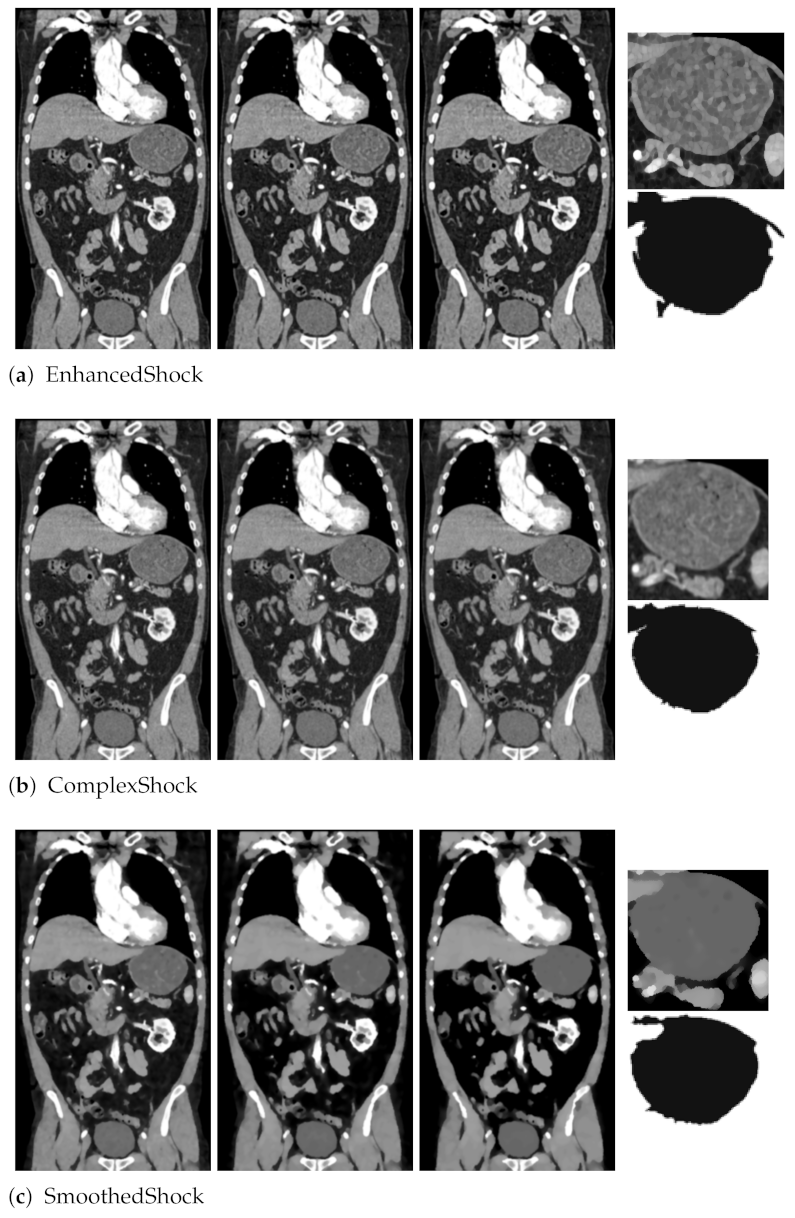

4.1. Image Segmentation